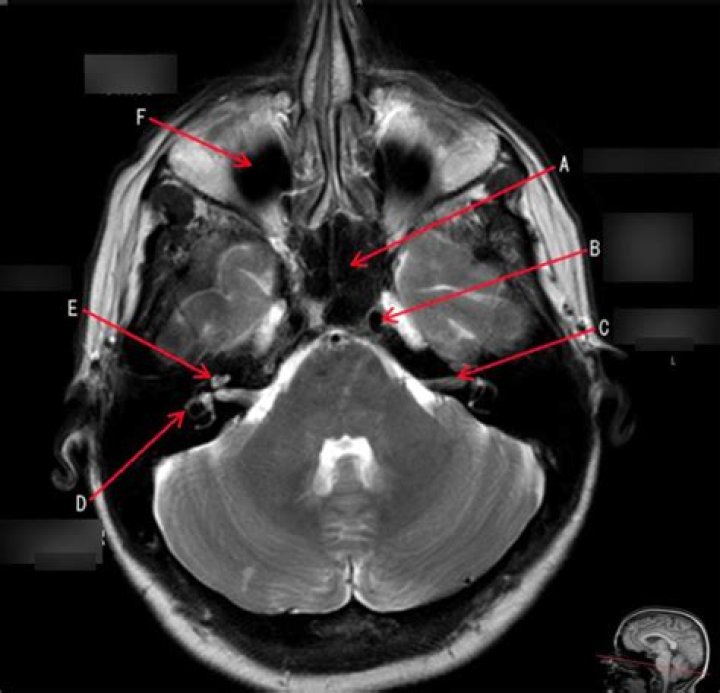

Magnetic resonance imaging (MRI) of the internal auditory canal (IAC) is a non-invasive, painless diagnostic imaging procedure that uses using radio waves and a strong magnetic field to create detailed images of the bony canal that transmits nerves and blood vessels from the base of the brain to the inner ear.

The internal acoustic canal (IAC), also known as the internal auditory canal or meatus (IAM), is a bony canal within the petrous portion of the temporal bone that transmits nerves and vessels from within the posterior cranial fossa to the auditory and vestibular apparatus.

Magnetic resonance imaging (MRI) is presently the study of choice for assessment of the internal auditory canal (IAC). MRI provides excellent assessment of the IAC and the bony changes occurring in the canal walls, and it provides excellent demonstration of the content of the canal.